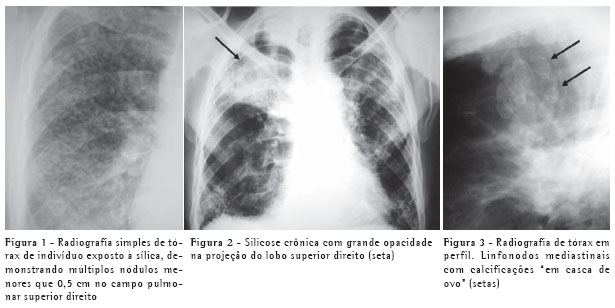

O padrão característico na radiografia é o de pequenos nódulos pulmonares circunscritos, menores que 0,5 cm, geralmente acometendo os campos pulmonares superiores, especialmente as regiões posteriores (Figura 1). Estes nódulos, com o passar dos anos, tendem à coalescência, com formação de grandes opacidades, maiores que 1 cm, o que é conhecido como silicose complicada (Figura 2). Estas podem estar acompanhadas de fibrose pulmonar (fibrose maciça progressiva), com redução volumétrica lobar, distorção arquitetural, retração hilar e fissural e aumento irregular dos espaços aéreos adjacentes.(3)

Podem também ser evidenciadas calcificações em linfonodos hilares ou mediastinais, por vezes periféricas, com padrão de "casca de ovo" (Figura 3).